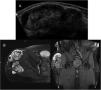

MRI images from this period show a homogeneous collection, markedly hyperintense on T2-weighted images, which fluctuates slightly in size, suggestive of postoperative seroma (Fig. 1A).

A) Axial T2-weighted image: hyperintense collection, with discrete variations in size over seven years, compatible with seroma. B) Ultrasound: lobulated lesion with well-defined borders, with a thick peripheral capsule and markedly heterogeneous content, without vascularisation on colour Doppler study. C) Axial T1-weighted image: increased signal intensity on T1-weighted sequences (*), corresponding to methaemoglobin and images compatible with clots. Peripheral capsule of tissue that is most likely fibrotic, markedly hypointense on all pulse sequences (→). D) MRI three months later; decreased signal on T1-weighted sequences suggesting subacute-chronic evolutionary changes of methaemoglobin, as well as mild clot growth. Hypointense peripheral capsule (→). E) The PET-CT study shows increased peripheral glucose metabolism, suggestive of an inflammatory process.

The patient reported pain during follow-up. An ultrasound (Fig. 1B) and an MRI (Fig. 1C) were performed, revealing a significant enlargement of the collection and findings compatible with rebleeding.

The MRI was repeated three months later (Fig. 1D), and the collection appeared more organised with septa, subacute-chronic evolutionary changes in methaemoglobin and slight growth of the clots.

PET-CT imaging revealed increased peripheral glucose metabolism, suggestive of an inflammatory process (Fig. 1E).

Given the patient’s oncological history, the case was reviewed by the hospital's sarcoma and bone tumour committee and a decision was made to perform an ultrasound-guided biopsy. The histological study showed organised haematic material and fibrin, with reactive connective tissue, compatible with a CEH.